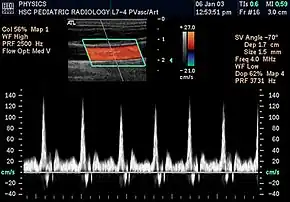

In the 1970s, Strandness and the bio-engineering group at the University of Washington, turned their attention to the use of real-time B-mode scanning. This type of ultrasound would enable physicians to see the vascular structures in real-time. Further research allowed B-mode imaging to be combined with Doppler ultrasound, providing real-time views of the vascular structures and simultaneous hemodynamic information. Today, this type of duplex scanning is used in a variety of ultrasound specialties.[6]

Prior to Strandness' work, the only vascular imaging available to physicians would have been arteriograms, x-rays read from radiopaque dyes injected directly into the bloodstream. Initially, the idea of using ultrasound imaging was met with resistance. Eventually, however, younger physicians were more receptive and accepting of the technology Strandness and his team developed. Although arteriograms are sometimes still used, most physicians today rely upon the non-invasive procedures and real-time information provided by duplex ultrasound scans.[9]

Today, based on the technologies and practices Dr. Strandness developed, vascular ultrasound is a well established field. Technologists, known as vascular sonographers, specialize in this specific branch of ultrasound scanning.[10]